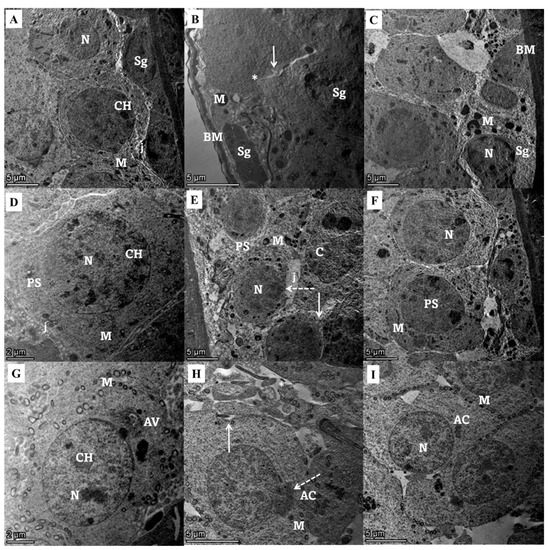

Ultrastructural examination of seminiferous tubular lining cells from different experimental groups showed a typical ultrastructural picture of spermatogenic, primary spermatocytes, and spermatid cells, while the group treated with gentamycin showed spermatogenic cells with irregular basement membrane with damage nuclear membrane and Swollen mitochondria, with loss of the tight junction in between the increasing intercellular gap. Primary spermatocytes with focal nuclear membrane damage beside numerous enlarged mitochondria and wide intercellular gap, and spermatids with membrane ruptured cell membrane with irregularly shaped to detached acrosomal cap with the enhancement of intracellular gaps. Marked improvement in the ultrastructural shape of seminiferous tubular cells with the treatment with Zamzam water in the form of spermatogenic cells with the normal basement membrane, nucleus, mitochondria, and minimal loss of the epithelial tight junction, slightly enlarged primary spermatocyte with nearly normal oval shape nucleus, regular nuclear membrane and many normal mitochondria, and spermatids with definite cell outline and typical cell to cell junction decreasing intracellular spaces (Figure 5).

Figure 5.

Transmission electron micrograph of seminiferous tubular lining cells from different experimental groups. (1) Spermatogonia cells (A) control group shows a normal arrangement of spermatogenic cells, including numerous spermatogonia (Sg) with normal nucleus (N) and peripherally arranged mitochondria (M), and chromatoid body (CH) and cells, showing Normal junction (j) in between. (B) Gentamicin group showing irregular basement membrane (BM), spermatogonia (Sg) with damaged nuclear membrane and compact Electron dense granule Swollen mitochondria (M), and irregular cell outline with loss of tight junction in between increasing intercellular gap (arrow). (C) Zamzam treated group showed normal basement membrane (BM), minimally enlarged spermatogonia (Sg) with nearly normal nucleus (N), and granular cytoplasm containing many small mitochondria (M); it appears as control with minimal loss of the epithelial tight junction. (2) Primary spermatocytes (D) Control group showing normal primary spermatocyte (PS) with prominent well-defined euchromatic nucleus (N), chromatoid body (CH), and fine cytoplasm containing many normal mitochondria (M) cells with tight junction (j). (E) Gentamicin group showing vacuolated primary spermatocyte with irregular cell outline (arrow) with focal nuclear membrane damage (dotted arrow) besides numerous enlarged mitochondria (M) and wide intercellular gap (arrow). (F) Zamzam treated group showed slightly enlarged spermatocytes with nearly normal oval shape nucleus (N), regular nuclear membrane, and many normal mitochondria. 3) Spermatids (G) control group showing normal spermatids with its characteristic complete acrosomal cap (AC) and acrosomal vesicles (AV). Its nucleus (N) is euchromatic with fine granular chromatin (CH) and peripherally arranged vesicular mitochondria (M). (H) Gentamycin group showing spermatids with irregular cell outline (shrunken) with membrane rupture (Arrow) and local distribution of some cytoplasmic irregular compact mitochondria (M) beside irregularly shaped (AC) to detached acrosomal cap (dotted arrow) multivaculation in intercellular space increasing intracellular gaps (*). (I) Zamzam treated group showing well-developed and activated spermatids with definite cell outlines and normally arranged mitochondria (M), cells show typical cell to cell junction decreasing intracellular spaces. (TEM, bar, 5 µm A,B,C,E,F,I. J.TEM, bar, 2 µm D,J).

In this research, testicular weight reduction in the gentamicin group was associated with alternation in histological and ultrastructural with severe spermatogenic vacuolation and pyknosis, with necrosis in spermatids and spermatozoa, and intraluminal clumped sloughed germ cells. These histopathological findings with subsequent loss of spermatozoa coincide with those of Narayana, [41] and Elsawah et al. [52]. The depletion of testicular glycogen content appeared as a weak PAS-positive reaction. Some authors explained this as the damaged cells’ loss of the capacity to metabolize the glycogen and its storage [53]. At the level of the ultrastructural study, gentamicin administration at 100 mg/kg for six days induced seminiferous different cells destruction in the form of an irregular basement membrane with the damaged nuclear membrane and swollen mitochondria, with loss of tight junction in between increasing intercellular gap with a detachment of spermatid acrosomal cap. These findings are in concurrence with Khaki et al. [54], who reported that gentamicin treatment caused testicular ultrastructural damage with mitochondria with lost cristae and lysosomes seen more in the cytoplasm of Sertoli cells. Drinking Zamzam water significantly (p < 0.05) improved testicular weight; this result is explained by two different mechanisms. First, its modulating effect on the pituitary-gonadal axis by significantly (p < 0.01) upregulating the level of testosterone level with the downregulation of FSH, and LH hormone improving the spermatogenesis process, and the second one is through its antioxidant property. The positive impact of Zamzam water on testicular weight matches with its modulatory effect on the morphological structure of the testes in the form of maturation of spermatogenic cells in the seminiferous tubules, with few vacuolated spermatogenic cells, abundant intraluminal mature sperm cells, normal interstitial space with apparently normal Leydig cells, increasing the glycogen content, and marked improvement in the ultrastructural shape of seminiferous tubular cells in the form of the normal basement membrane, nucleus, mitochondria, and minimal loss of the epithelial tight junction. This study revealed that treatment with gentamicin significantly (p < 0.001) altered the spermatic parameters as it reduced the motility of sperm and its progressive motility, increased the percentage of dead sperm and abnormal forms of the sperm either in the head, middle piece, or in tail pieces in relation to control rats. There is a considerable correlation between the motility and viability of the sperm, as the nonviable sperm loses the motility capacity. These ominous signs can be attributed to its inhibitory effect on testosterone with impaired epididymis maturation, which can also be explained by gentamicin-induced oxidative stress [55]. The toxicity of gentamicin on the spermatic parameter coincides with the study reported by Kim et al. [5]. Coadministration of Zamzam water with gentamicin significantly (p < 0.001) improved the sperm parameter and motility, decreasing the percentage of dead sperm and abnormal forms, which can be explained by its scavenging power on oxygen free radicals.